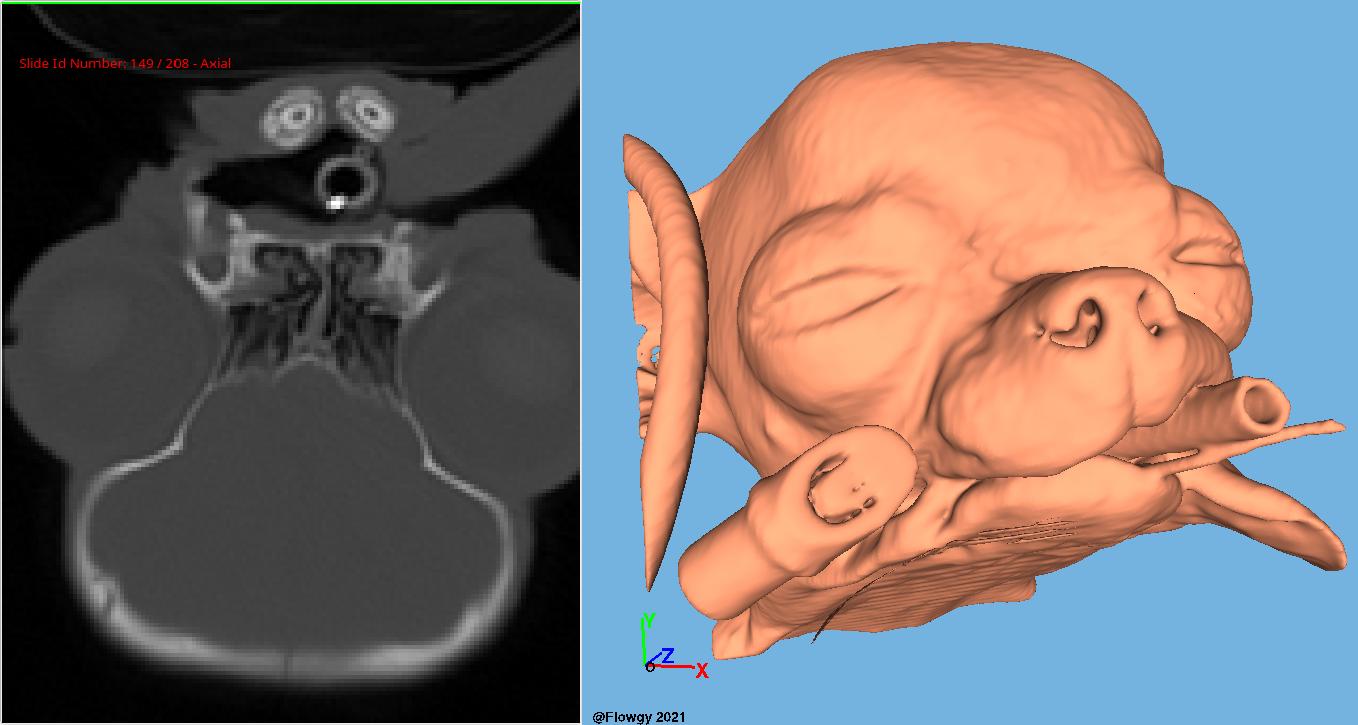

At Flowgy, we recognize the importance of innovation and continuous education in the field of otolaryngology (ENT). Our platform integrates Computational Fluid Dynamics (CFD) techniques and virtual surgery to simulate nasal airflow, offering a deeper and more detailed understanding of nasal respiratory dynamics.

Use CFD simulations to investigate nasal pathologies and advance scientific understanding of airflow dynamics.

Simulate surgical interventions virtually to develop and refine new techniques before applying them in clinical settings.